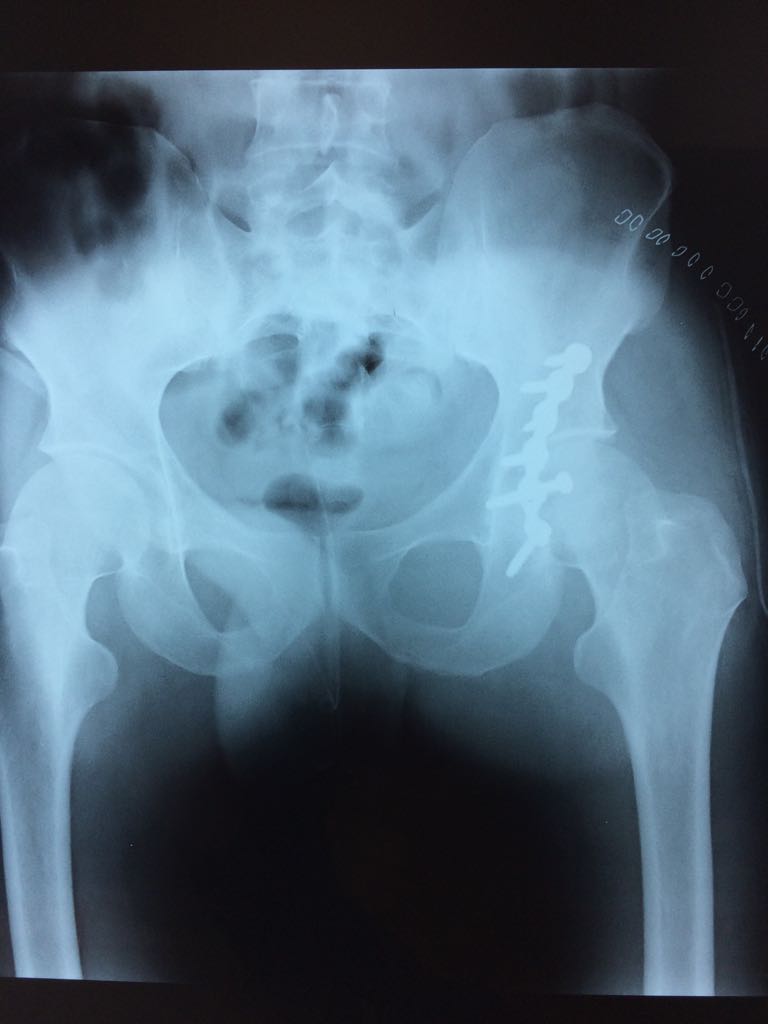

- Una frattura di bacino in un Calatino:

Postoperatorio